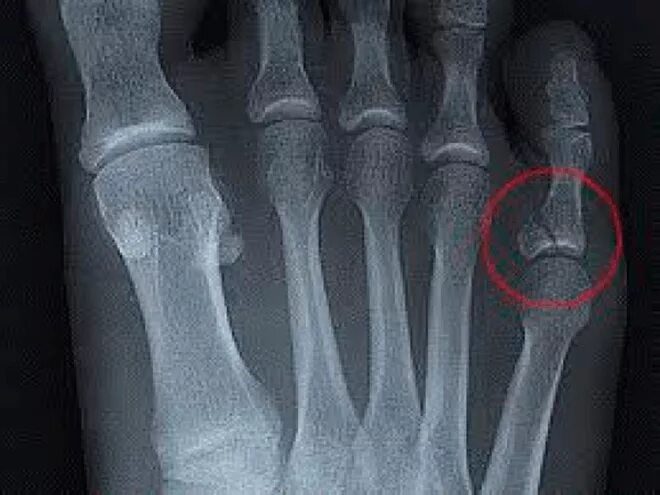

Закрытый перелом пальцев стопы мкб 10